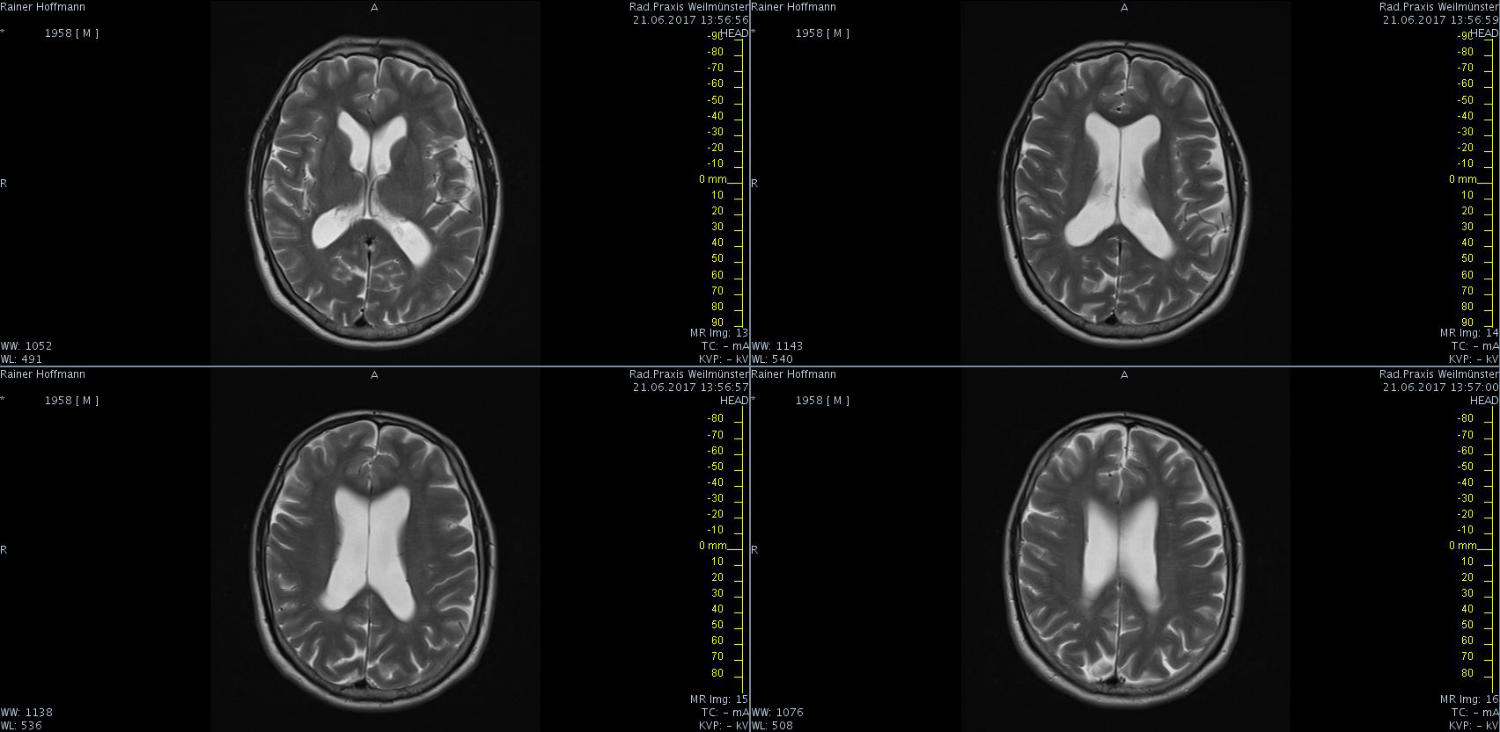

Das ist ja ganz toll, dass Ihr die Seite so schnell gefunden habt. Ich zeige euch jetzt ein ganz, ganz anderes Paßfoto von mir. Es könnte Ähnlichkeiten zu anderen lebenden oder bereits verstorbenen Personen geben. Wenn Ihr das erste Bild oben links anklickt wird es ver- größert dargestellt. Dann kann man mit den Pfeiltasten am unteren Bild- rand durch meinen Kopf blättern. Es gibt nicht viel zu sehen. Vielen Dank an Martina für Ihre Hilfe.

MRT